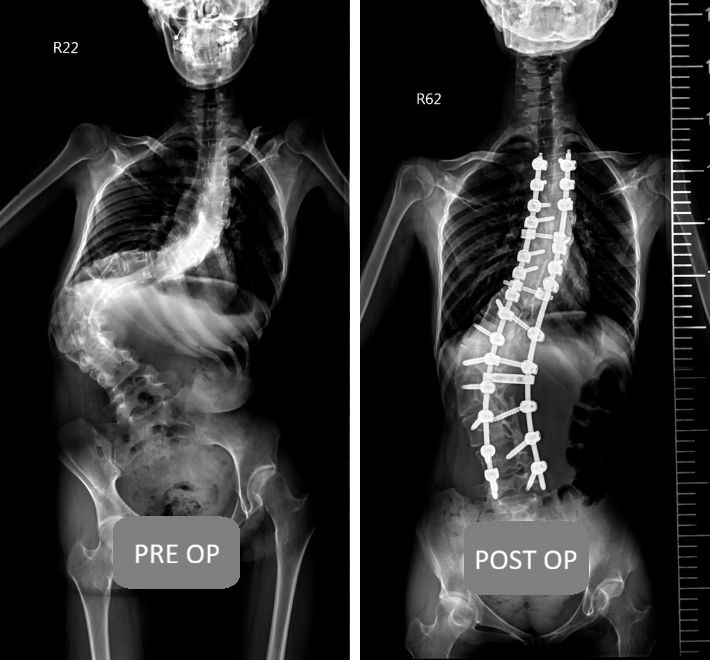

1. Traditional Technique: Posterior Spinal Instrumentation and Fusion (The Gold Standard)

While modern minimally invasive techniques are prevalent, traditional open surgery remains the ideal approach for treating extremely severe deformities or multi-level complex curves.

Principle: A midline incision is made on the back, muscles are retracted to provide a clear field of view, screws are implanted, corrective osteotomies are performed, and bone graft is added to achieve fusion.

Advantages: Provides the strongest corrective force and the most direct visual field, making it suitable for complex cases with curves greater than 70°.

Disadvantages: Larger incision (typically 15-30 cm), greater blood loss, and more significant muscle disruption.